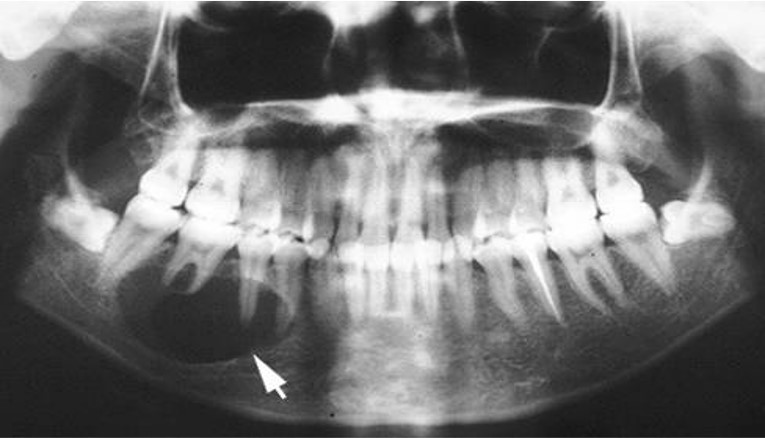

20~60岁之间,下颌多见,前磨牙和磨牙区最为常见,患者无特殊症状,仅见颌骨逐渐膨胀,X线显示不规则透射区内含大小不等的阻射性团块(图14.1-14)。

图14.1-14 牙源性钙化上皮瘤(X线)